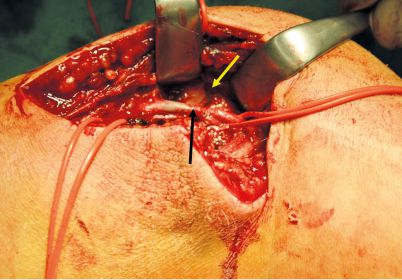

Schnittführung in der rechten Ellenbeuge mit eingebluteter Subcutis. Die A. brachialis war nach Entfernung eines Kirschner-Drahtes zu identifizieren – es zeigte sich insbesondere, dass die A. brachialis

in dem Knochenspalt eingeklemmt war. Durch Auseinanderdrängen des Knochenspaltes konnte das Gefäß freigelegt und das Hämatom ausgeräumt werden, wodurch sich die perforierte Wandläsion der A. brachialis dextra darstellte (Abb. 2), die mit 7-0 Prolene-Naht (Ethicon, Norderstedt/Deutschland) versorgt wurde. Die Arterie zeigte sich gut pulsierend. Einlage von Gelasponstreifen ins OP-Gebiet und Platzierung einer Mini-Redon-Drainage in die rechte Ellenbeuge. Anschließend erfolgte der schichtweise Wundverschluss subkutan mittels Vicryl 3-0 (Ethicon), Hautverschluss mit einem resorbierbaren Faden (5-0) Einzelknopfnaht, gefolgt von Wunddesinfektion und sterilem Verband. Anlage einer Gipsschiene durch den Kinderchirurgen. Die postoperative Kontrolle mittels Doppler-Sonde zeigte gut detektierbare Pulse der A. radialis und A. ulnaris rechts.

Abb. 2: Intraoperativer Op-Situs eines

ähnlichen Falles: Frakturspalt (gelber Pfeil)

und thrombosierter verletzter Gefäßabschnitt (schwarzer Pfeil) der A. brachialis

(Foto: mit freundlicher Genehmigung von

Prof. Dr. Halloul, Arbeitsbereich Gefäßchirurgie, Klinik für Allgemein-, Viszeral-, Gefäß- und Transplantationschirurgie, Universitätsklinikum Magdeburg A. ö. R.)